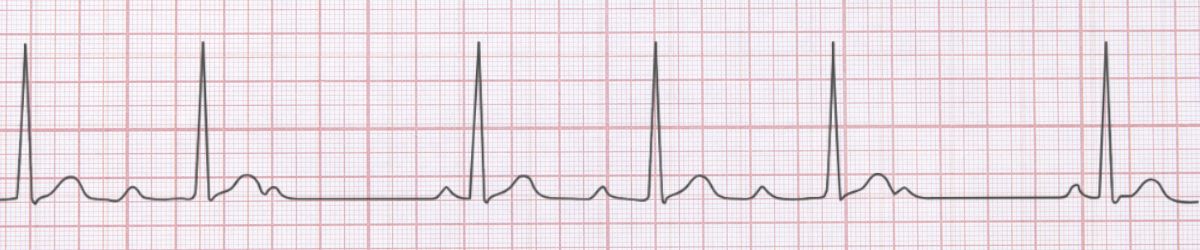

Image First Degree AV Block ECG Example Figure 1: First Degree AV Block - Characteristic ECG Pattern

πŸ“Š Diagnostic ECG Criteria

• PR interval >0.20 seconds

• Every P wave conducted

• 1:1 AV conduction

• Regular rhythm

First Degree AV Block is characterized by pr interval >0.20 seconds and every p wave conducted. Usually benign, may indicate AV nodal disease, can progress to higher degrees Management priority: Monitor for progression, identify reversible causes (medications, ischemia) Key takeaway: Recognition and reassurance are the primary interventions needed